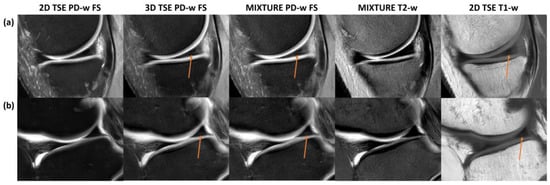

Across the acquired sequences, cartilage demonstrated an intermediate signal intensity and a layered zonal structure (Figure 2 and Figure S1). However, the ROI-based analysis yielded a significantly more pronounced contrast as evidenced by significantly more negative Weber contrast values between cartilage and synovia for the 2D TSE images (p < 0.001 [Figure 3a]). In visual terms, the negative Weber contrast values translate into a darker presentation of the cartilage tissue than the bright synovial fluid. Similarly, CNR values tended to be higher in the 2D TSE images, though not significantly (Figure 3b), and CV values were largely similar (Figure 3c).

Figure 2. For a representative slice (through the central lateral femorotibial compartment) and joint, the 2D TSE image (a), the 3D TSE image (b), and the MIXTURE image (c) are shown alongside the MIXTURE T2-weighted image (d), the MIXTURE T2 map (e), and the segmented cartilage tissue overlay (f). In this example, the segmented femoral and tibial cartilage exhibited T2 relaxation times of 48 ± 18 ms and 36 ± 16 ms, respectively (mean ± standard deviation). In areas of fatty tissue, the MIXTURE T2 map did not yield meaningful values because SPAIR fat saturation was employed during the acquisition of the PD-weighted FS morphologic images. Abbreviations: PD—proton density, -w—weighted, FS—fat-saturated, MIXTURE—Multi-Interleaved X-prepared Turbo Spin-Echo with IntUitive Relaxometry, SPAIR—Spectral Attenuated Inversion Recovery. Figure S1 provides a close-up of the femoral and tibial cartilage of the weight-bearing region.